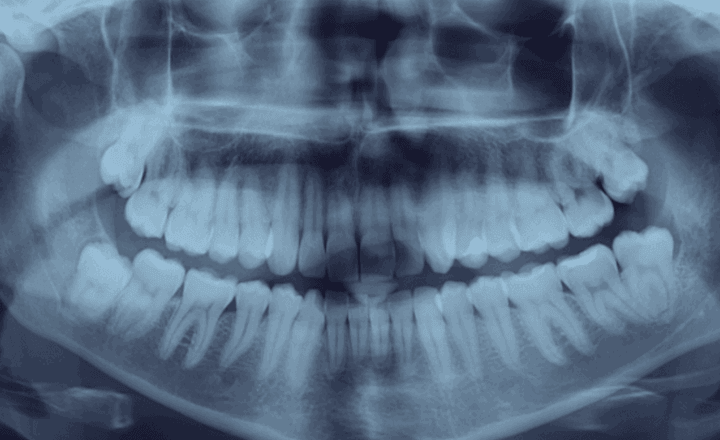

Навряд чи хтось дуже зрадіє, якщо стоматолог порекомендує видалення зубів . Але бувають ситуації, коли доводиться це зробити. У стоматологічному центрі White Clinic до такої процедури вдаються лише в крайніх випадках, коли інші методи лікування неможливі. Це означає, що спочатку дантисти намагаються зберегти зубну одиницю за допомогою сучасних технологій. Але якщо лікар все-таки запропонував екстракцію, варто бути готовим до того, що може очікувати після хірургічного втручання.